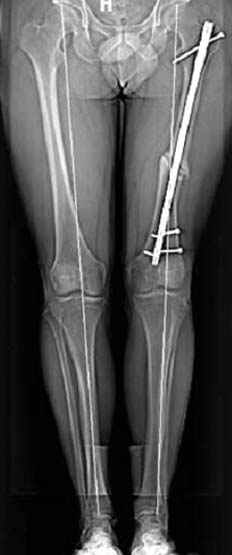

Несколько снимков из моей коллекции, чтобы разьяснить, почему мы до сих пор делаем различные варианты остеотомии.

На рисунке N1 предоперационный план лечения ложного сустава шейки бедра- линия ложного сустава, угол и направление введения импланта, клиновидная остеотомия в градусах и миллиметрах, второй снимок после коррекции, расчет, на сколько удлиняется конечность и размеры импланта;

N3 рисунок окончательный снимок, после операции моя рентгенограмма должен выглядеть примерно как эта картина. На N4 снимке клин перед удалением; N5 послеоперации 3 нед.; N6 окончательная рентгенограмма.

(доложен в Ст. Петербурге 2003 и в Москве 2004)

варус при проксимальном отделе 95 градусной пластиной.

пластическая модель; и коррекция бедра аппаратом Илизарова.